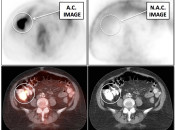

Attenuation Correction (AC) Artifacts:

On occasion (typically in older PET/CT machines), attenuation correction of PET images can result in falsely elevated metabolic activity in regions of high CT density (e.g. metallic devices, oral contrast, calcification). In such cases, these areas must be reviewed on the NAC (non-attenuation correction) images. If these regions are not also hypermetabolic on the NAC images, then their apparent increased FDG-uptake on the AC images is artifactual (addressed in detail, here).